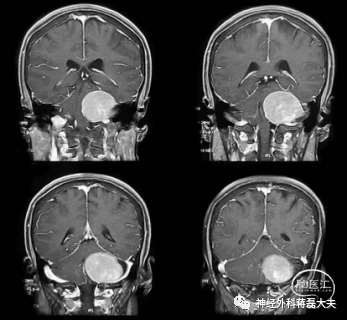

神经外科蒋磊教授带领团队充分讨论,患者术前喉镜示左侧声带运动麻痹,头颅MRI检查发现桥小脑角巨大肿瘤,紧邻脑干,与舌咽面神经、迷走神经等后组颅神经关系密切。蒋磊教授指出肿瘤体积巨大,但从影像学判断为良性脑膜瘤,直径6cm,已经明显压迫脑干颅神经导致吞咽困难、声音嘶哑和左侧声带麻痹,由于肿瘤巨大已经严重压迫脑干和小脑导致行走不稳,必须尽快手术,以防出现生命危险。

考虑到患者术前已经出现后组颅神经受损,手术更需仔细轻柔操作,最大程度保护颅神经、脑干和小脑功能。蒋磊主任与家属充分沟通,经家属同意,最终决定在神经电生理监测下行左侧乙状窦后入路开颅手术切除肿瘤。